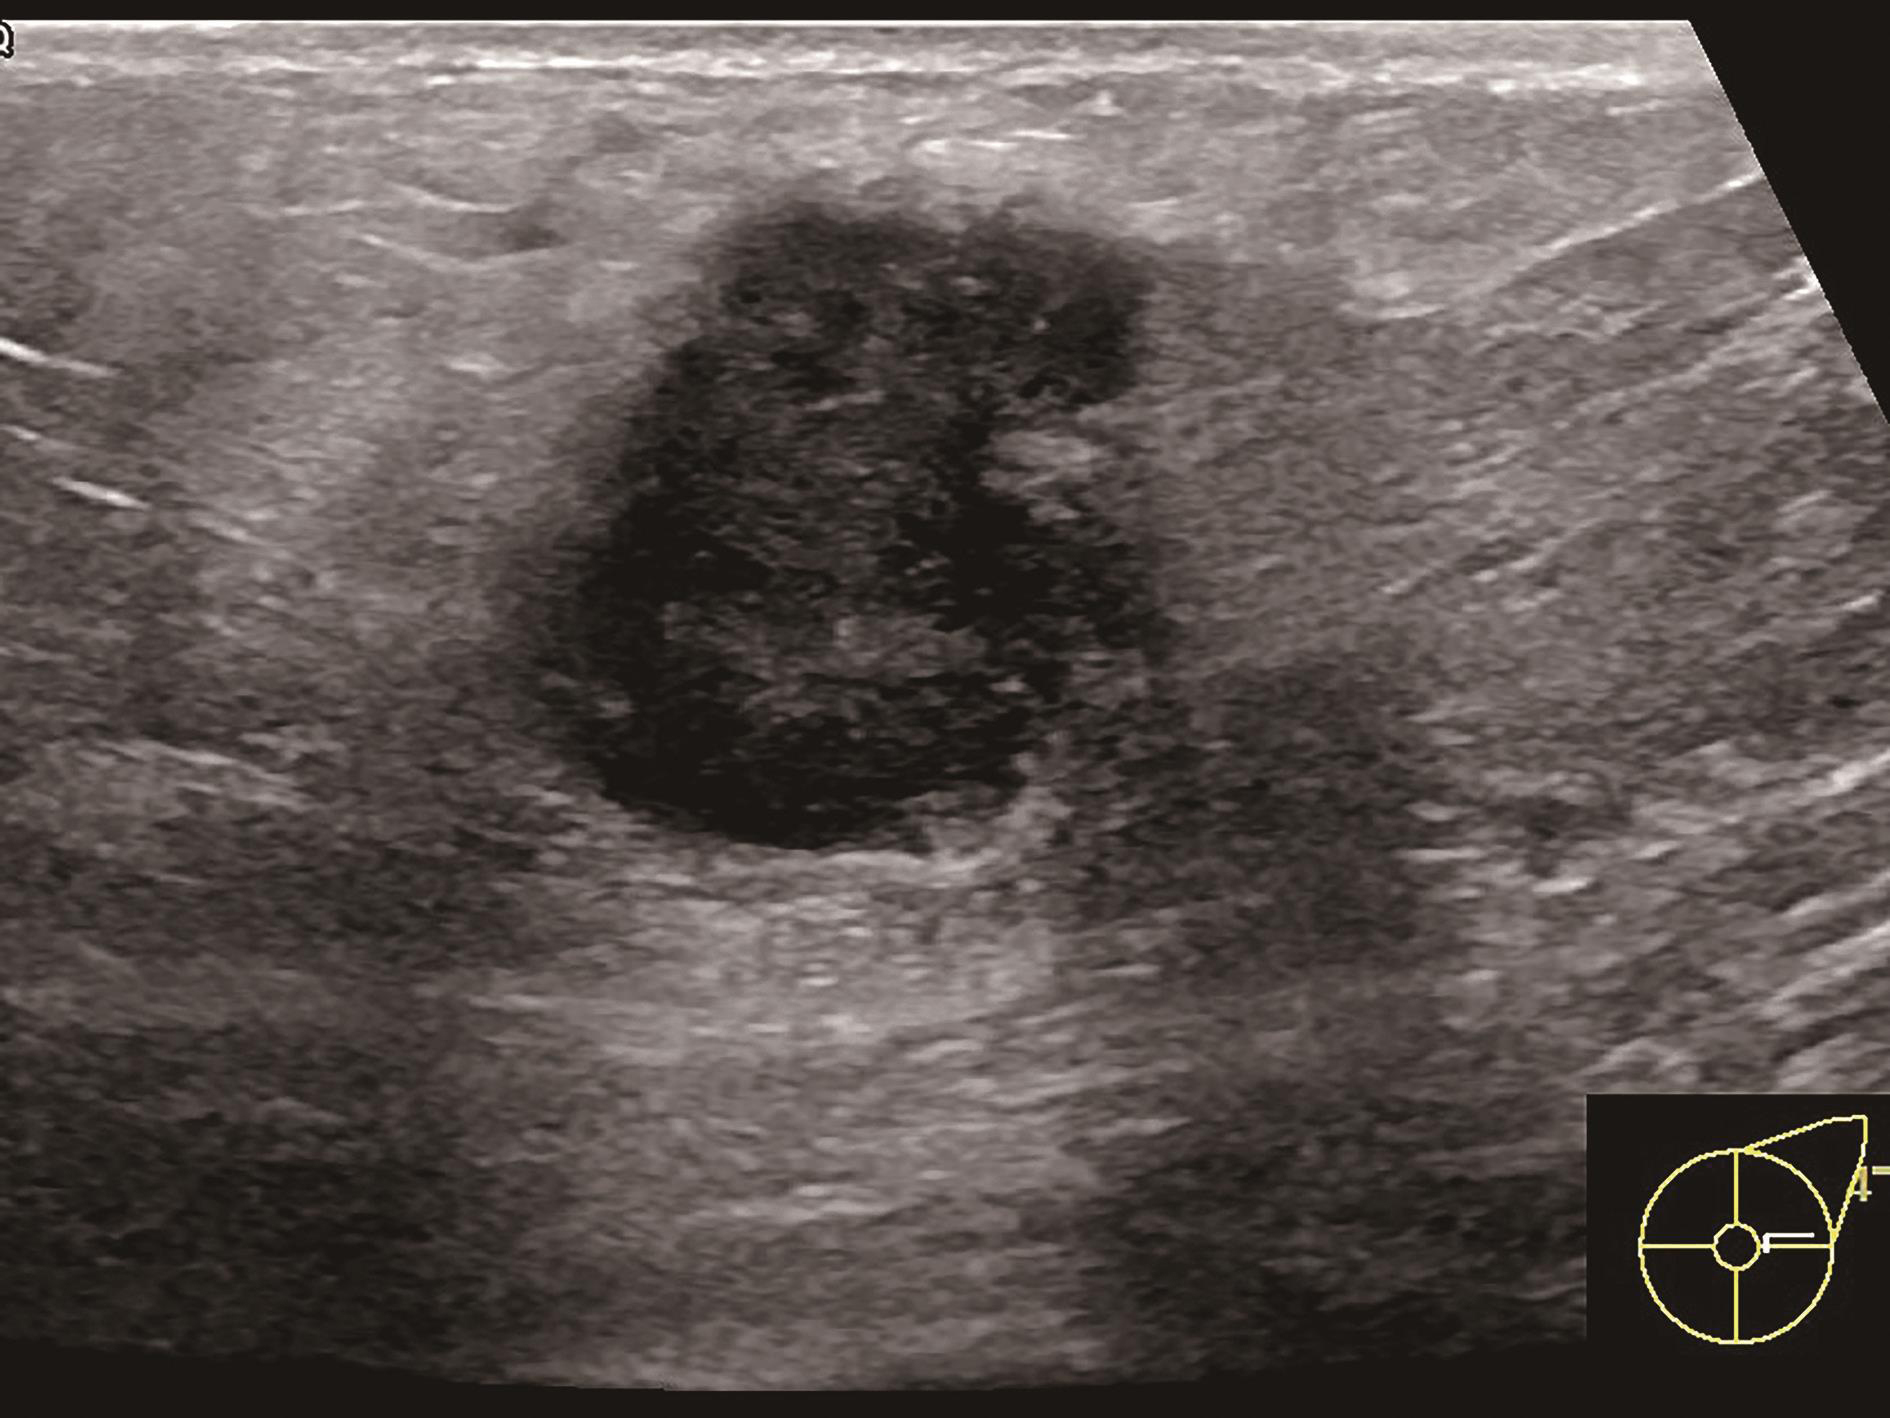

内部透声差的乳腺囊性病变,或呈奶酪样改变的积乳囊肿,乳腺血肿或脂肪坏死,有时难以与真实性结节相鉴别,或乳腺实性病变表现为极低回声,难以与囊性病变鉴别时,超声造影可以作出明确诊断。

5.乳腺造影增强模式受多种情况影响,与病灶的发展阶段、分化程度、乳腺是否处于增殖期或哺乳期都有关系。如乳腺恶性肿瘤在其发展过程中会经历少血管期、富血管期(图2-2-11),尤其是当肿瘤还较小时,可能新生血管尚未形成,超声造影可表现出等增强甚至低增强,而在富血管期可表现出典型的快进高增强,而有出血坏死时可表现出无增强。同时,在同一非均质性病灶内,不同部位、不同回声类型及不同彩色血流表现的切面,造影也可表现出不一样的增强模式,所以拥有扎实的乳腺普通灰阶超声诊断基础是进行乳腺超声造影的前提。尽管乳腺超声造影表现复杂且多种多样,但基于6类乳腺超声造影良恶性预测模型(详见第三章第三节)进行判读可以解决大多数临床问题。